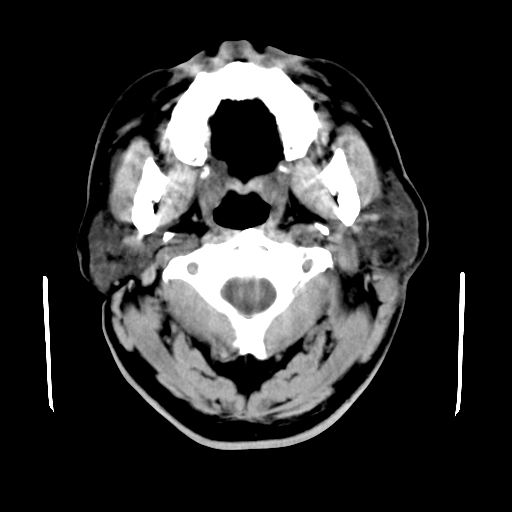

以下是引用卜一在2007-8-6 21:23:00的发言:[br]定位:左侧胸锁乳突肌内侧 颌下腺下后方。特征:弥漫性生长 软组织密度肿块,界限不清,内隐约见低密度坏死。考虑:神经源性肿瘤或血管源性肿瘤。

以下是引用wangzhanshuang在2007-8-6 21:08:00的发言:[br]腮腺混合瘤